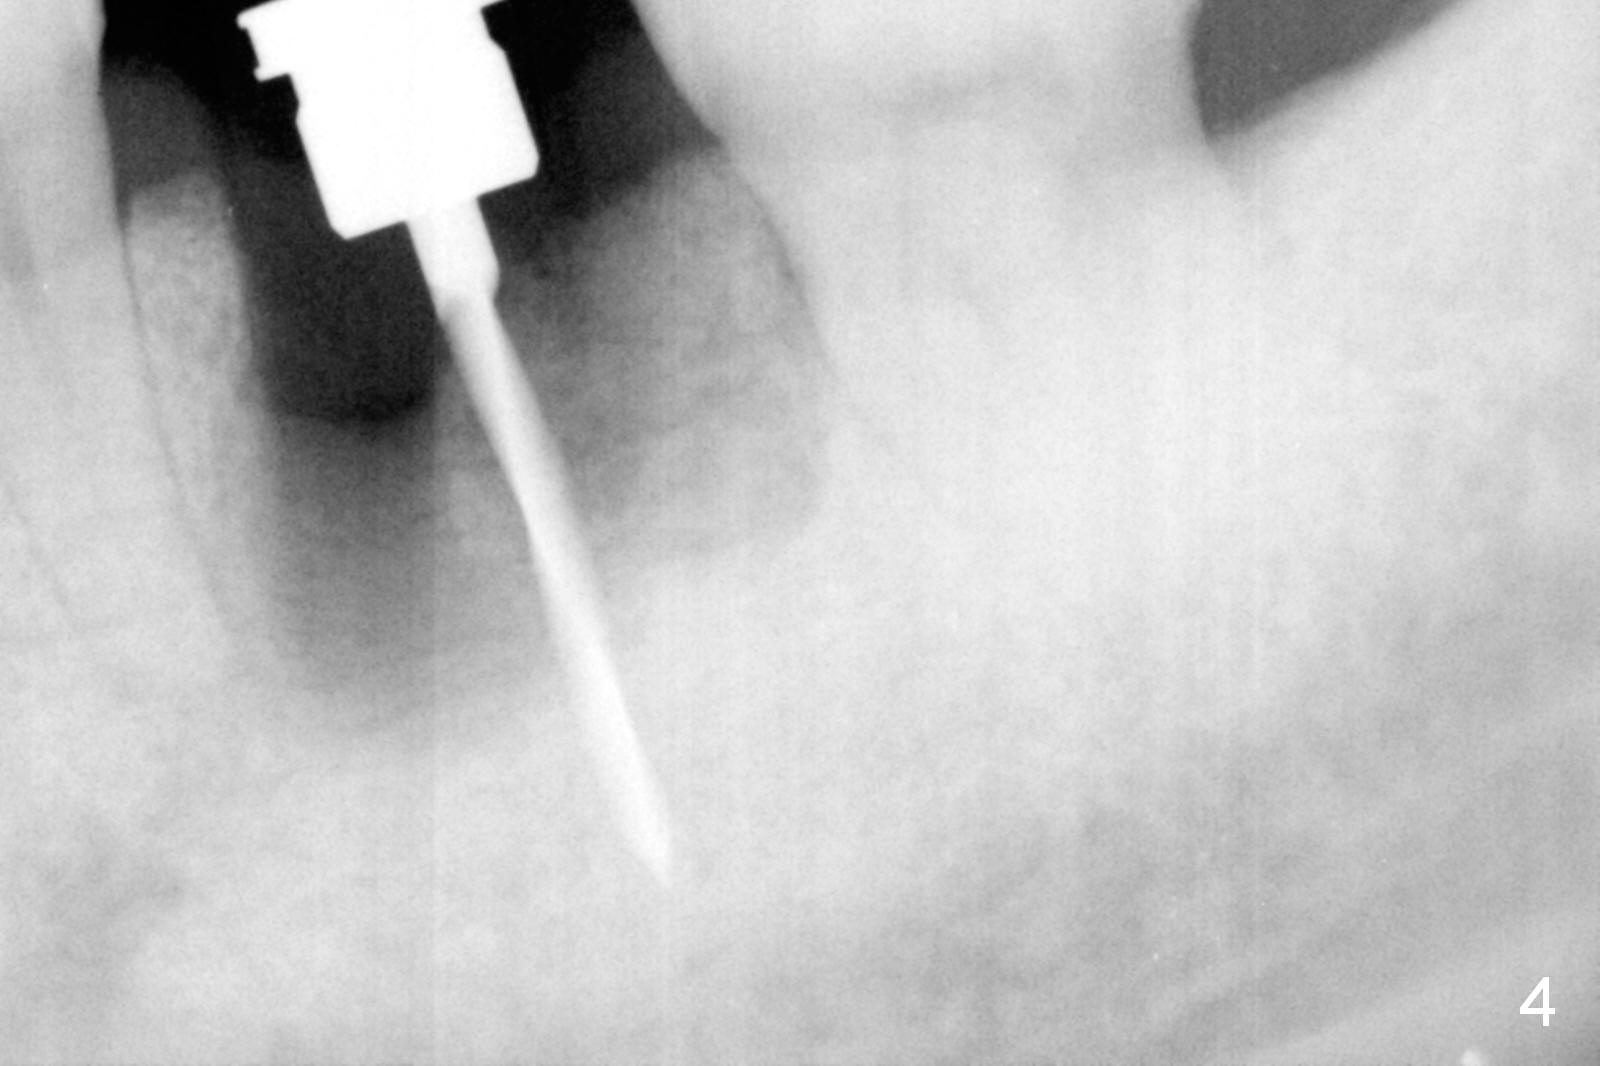

The asymptomatic tooth (#19) has a midbuccal fistula (Fig.1 <). The mesiobuccal pocket is 10 mm with purulent discharge from the sulcus (Fig.2,3). The mesiobuccal wall defect is confirmed when the tooth is extracted. Osteotomy is initiated lingually in the septum following septal crestoplasty (flattening) (Fig.4: using 1.6 mm drill for 9 mm). Since the lingual portion of the osteotomy is higher, it is difficult to use drill with stopper. For the narrow septum osteotomy, multiple drills are used sequentially (Fig.5 after 4.3 mm drill). A 4.5x11 mm dummy implant is placed (Fig.6) apparently too deep. When a 5x11 mm IBS implant is being placed, the depth is tightly controlled (Fig.7). The implant is apical to the lingual crest, whereas there is ~ 2 mm implant exposure buccally. That is, there is a large gap mesiobuccally (Fig.8), which is filled with .5-1.5 mm allograft (Fig.9 *). A 6.5x5.7(3) mm abutment (A) is placed and trimmed for an immediate provisional (Fig.10 P). The lacerated buccal gingiva is sutured as well as application of Perio Glue.